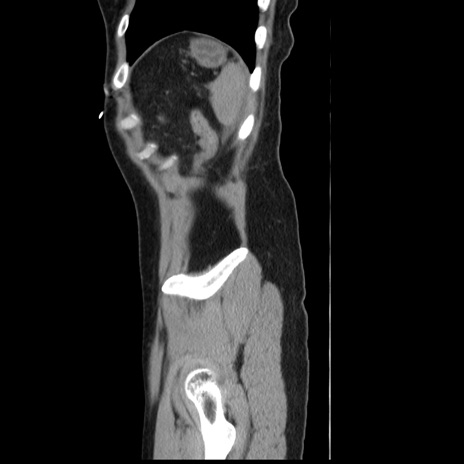

横断像

【症例】 50歳代女性

【主訴】 腹痛

【現病歴】前日生レバーを食べた。今朝に排便あり。 昼前に突然発症の腹痛を生じ、当院救急外来を受診した。

【既往歴】 子宮筋腫にてで子宮全摘後

【身体所見】 意識清明、腹部:平坦、軟、下腹部やや左を中心に圧痛・反跳痛あり、筋性防御あり

【データ】WBC 7800、CRP 0.07